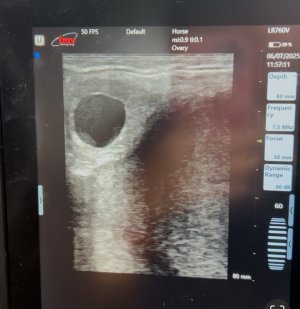

Took both mares for a quick check and scan. We had seen Aria come into season this week, and vets confirmed a decent CL. Wanted semen today. So fortunately managed to get that sorted. But, on scanning her the vet found a decent amount of blood, que panic that she had a rectal lining tear. So antibiotics to stop an infection, which could have led to peritonitis/death.. Semen arrived and vet says its like rocket fuel. Vets updating me twice a day, and Aria is all good, no blood in poo at all. They cant scan her until shes ready for a heart beat scan now, just to give a tear chance to heal. Going forward she will need to be slightly sedated for scanning so she doesnt push against it.